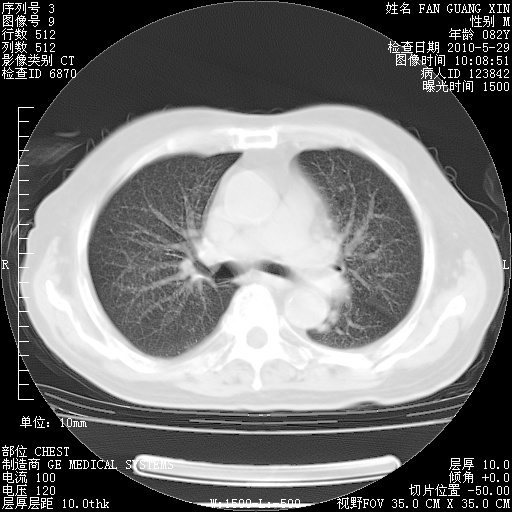

再治疗10天后的肺部CT

再治疗10天后的肺部CT 纵膈窗

阅读此次胸部CT,肺间质渗出性改变较入院时有吸收。目前从体温、白细胞、中性分叶明显增高,肯定存在细菌感染(发生医院感染哦,若无消化道及泌尿系统等感染的依据,肺部感染可能大)。若你院头孢哌酮舒巴坦钠耐药率较高,同意你的方案,若48小时体温仍高,可考虑使用碳青霉稀类抗菌药物,同时可予超声雾化、注意滴数时加大液体量。白蛋白33.30g/L较低哦,需加强营养等支持治疗。